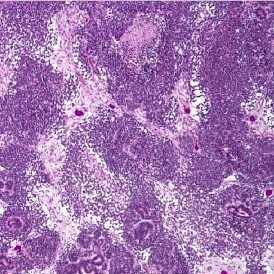

The IHC Tumor-Macrophages App provides tissue detection, including the separation of tumor and healthy tissue. It detects macrophages based on specific staining (e.g., CD68) and outputs the area of macrophages within tumor and healthy tissue.

Image: Courtesy of Dr. Patrick Michl, Dr. Maren Egidi, and Dr. Heidi Griesmann, Universitätsklinikum Halle (Saale).